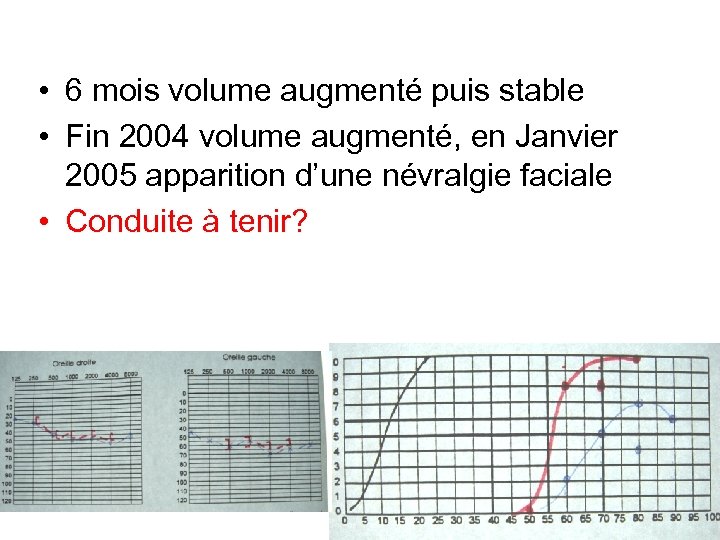

• 6 mois volume augmenté puis stable • Fin 2004 volume augmenté, en Janvier 2005 apparition d’une névralgie faciale • Conduite à tenir? 2002 2004

• 6 mois volume augmenté puis stable • Fin 2004 volume augmenté, en Janvier 2005 apparition d’une névralgie faciale • Conduite à tenir? 2002 2004

• 6 mois volume augmenté puis stable • Fin 2004 volume augmenté, en Janvier 2005 apparition d’une névralgie faciale • Conduite à tenir?

• 6 mois volume augmenté puis stable • Fin 2004 volume augmenté, en Janvier 2005 apparition d’une névralgie faciale • Conduite à tenir?